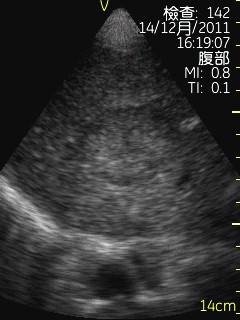

Vscan临床图片 腹部